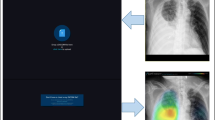

Simulation sessions in this study were designed based on the study site’s process for patient management in the ED. Performance assessment was conducted with each participant in a separate room and under a researcher’s supervision. Participants were asked to interpret CR findings presented alongside the patients’ demographic and clinical characteristics (age, sex, chief complaint, vital signs, and laboratory test results at admission). CRs in the anteroposterior and posteroanterior views were provided; in cases where previous CRs were available, they were provided at the same time. Clinical information of the patient and performed CRs were provided to the participants through a monitor screen. The simulation session comprised two steps, each of which was recorded through a web-based form (Google forms; Google, Mountain View, CA). In the first step, participants were asked to examine the given CR for abnormalities and to make a clinical decision regarding patient disposition based on the provided clinical information without DLCR. In the second step, participants performed simulation on the same case after being added the DLCR from the first step. At this stage, participants were not allowed to modify their responses provided in the first step; all responses were recorded in real-time. There was no time limit for the participant to complete the simulation (Fig. 1).

Representative case for performance assessment. (Left) CRs and the patients’ clinical and demographic characteristics were presented to the participating ED physicians in the first step. (Right) In the second step, the same information was presented, although the assessment was made using DLCR. CR, chest radiograph; ED, emergency department; DLCR, deep learning-based assistive technology on CR interpretation

All CR data used in the present study were analysed using commercially available DLCR (Lunit INSIGHT for Chest Radiography, version 4.7.2; Lunit; available at http://insight.lunit.io), approved by the Korea Food and Drug Administration for clinical use. This algorithm was developed to detect three major abnormalities (lung nodule, consolidation, and pneumothorax), with suspicious lesions within target regions displayed as a heat map with the corresponding abnormality scores provided as percentage values at the bottom of the image. The abnormality score represents the maximum probability value estimated for the finding of a lung nodule, consolidation, or pneumothorax, as determined by the programme itself. A single performance test of the algorithm using CR data from 244 patients was previously conducted by the Korea Food and Drug Administration, with a reported AUROC of 0.994 (95% CI 0.987–1.000), sensitivity of 97.26%, and specificity of 92.86%. The probability score for the high-sensitivity cut-off used in this test was 0.15. The deep learning algorithm receives a CR as input and then generates a heat map. This algorithm is composed of 120 convolutional layers with four dense blocks [21] and three parallel classifiers for each abnormality. In the training stage, the algorithm was trained to classify abnormal CRs and localize the region of the abnormalities. Two types of loss functions were used to train the algorithm: classification loss and localization loss. Given an input CR with annotations for the lesion location, the loss function for each abnormality was defined as the sum of the classification loss and localization loss. The classification loss was defined as the binary cross-entropy between the label of CR and the max-pooling of the corresponding probability map. The localization loss was defined as the average pixel-wise binary cross-entropy between the annotation on CR and the corresponding probability map. The losses of the three abnormalities were then finally summed to form the final loss function. In the case of CR inputs without annotation, only the classification loss was utilized. To predict lesion location, even without location information, a weakly-supervised localization scheme was used to train the classification loss. All of the hyperparameters were initialized randomly via Gaussian distribution and optimized using the stochastic gradient descent (SGD) with a mini-batch size of 64. A learning rate of 0.01 and a momentum term of 0.9 was used to stabilize the training, and the learning rate decreased from 0.01 to 0.001 after 30 epochs. The models were trained up to 40 epochs.